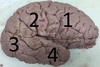

1. Identify the structure labelled 1. 2. Identify the structure labelled 2. 3. Identify the structure labelled 3. 4. Identify the structure labelled 4.

1. Frontal 2. Parietal 3. Occipital 4. Temporal